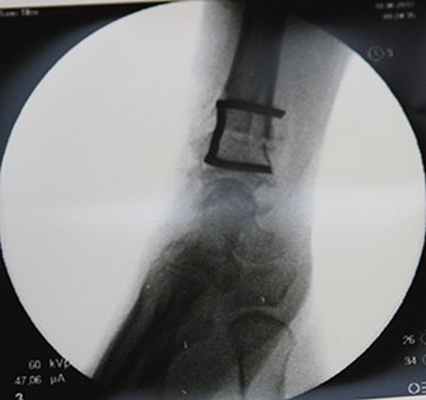

Снимок после укорочения лучевой кости

Элегантный способ фиксации остеотомии скобкой.

При обнаружении некроза полулунной кости почти всегда я рекомендую начинать с остеотомии лучевой кости. Это относительно безопасная и весьма эффективная операция. Она заключается в пересечении лучевой кости (пилой или остеотомом) с последующей ее фиксацией. При этом сам кистевой сустав и кости запястья даже не затрагиваются. Плюсы в том, что мы, не вмешиваясь в поврежденный сустав, можем значительно улучшить его функцию.

Вернемся к нашей героине, которая столкнулась с проблемой запястья накануне свадьбы. За месяц до намеченной даты была выполнена операция — остеотомия лучевой кости.